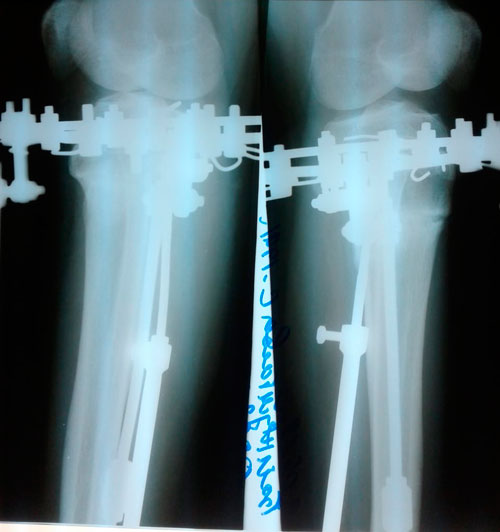

Дата операции - 04.03.2019г.

Дата снятия аппаратов - 03.06.2019г.

Срок сращения - 90 дней.